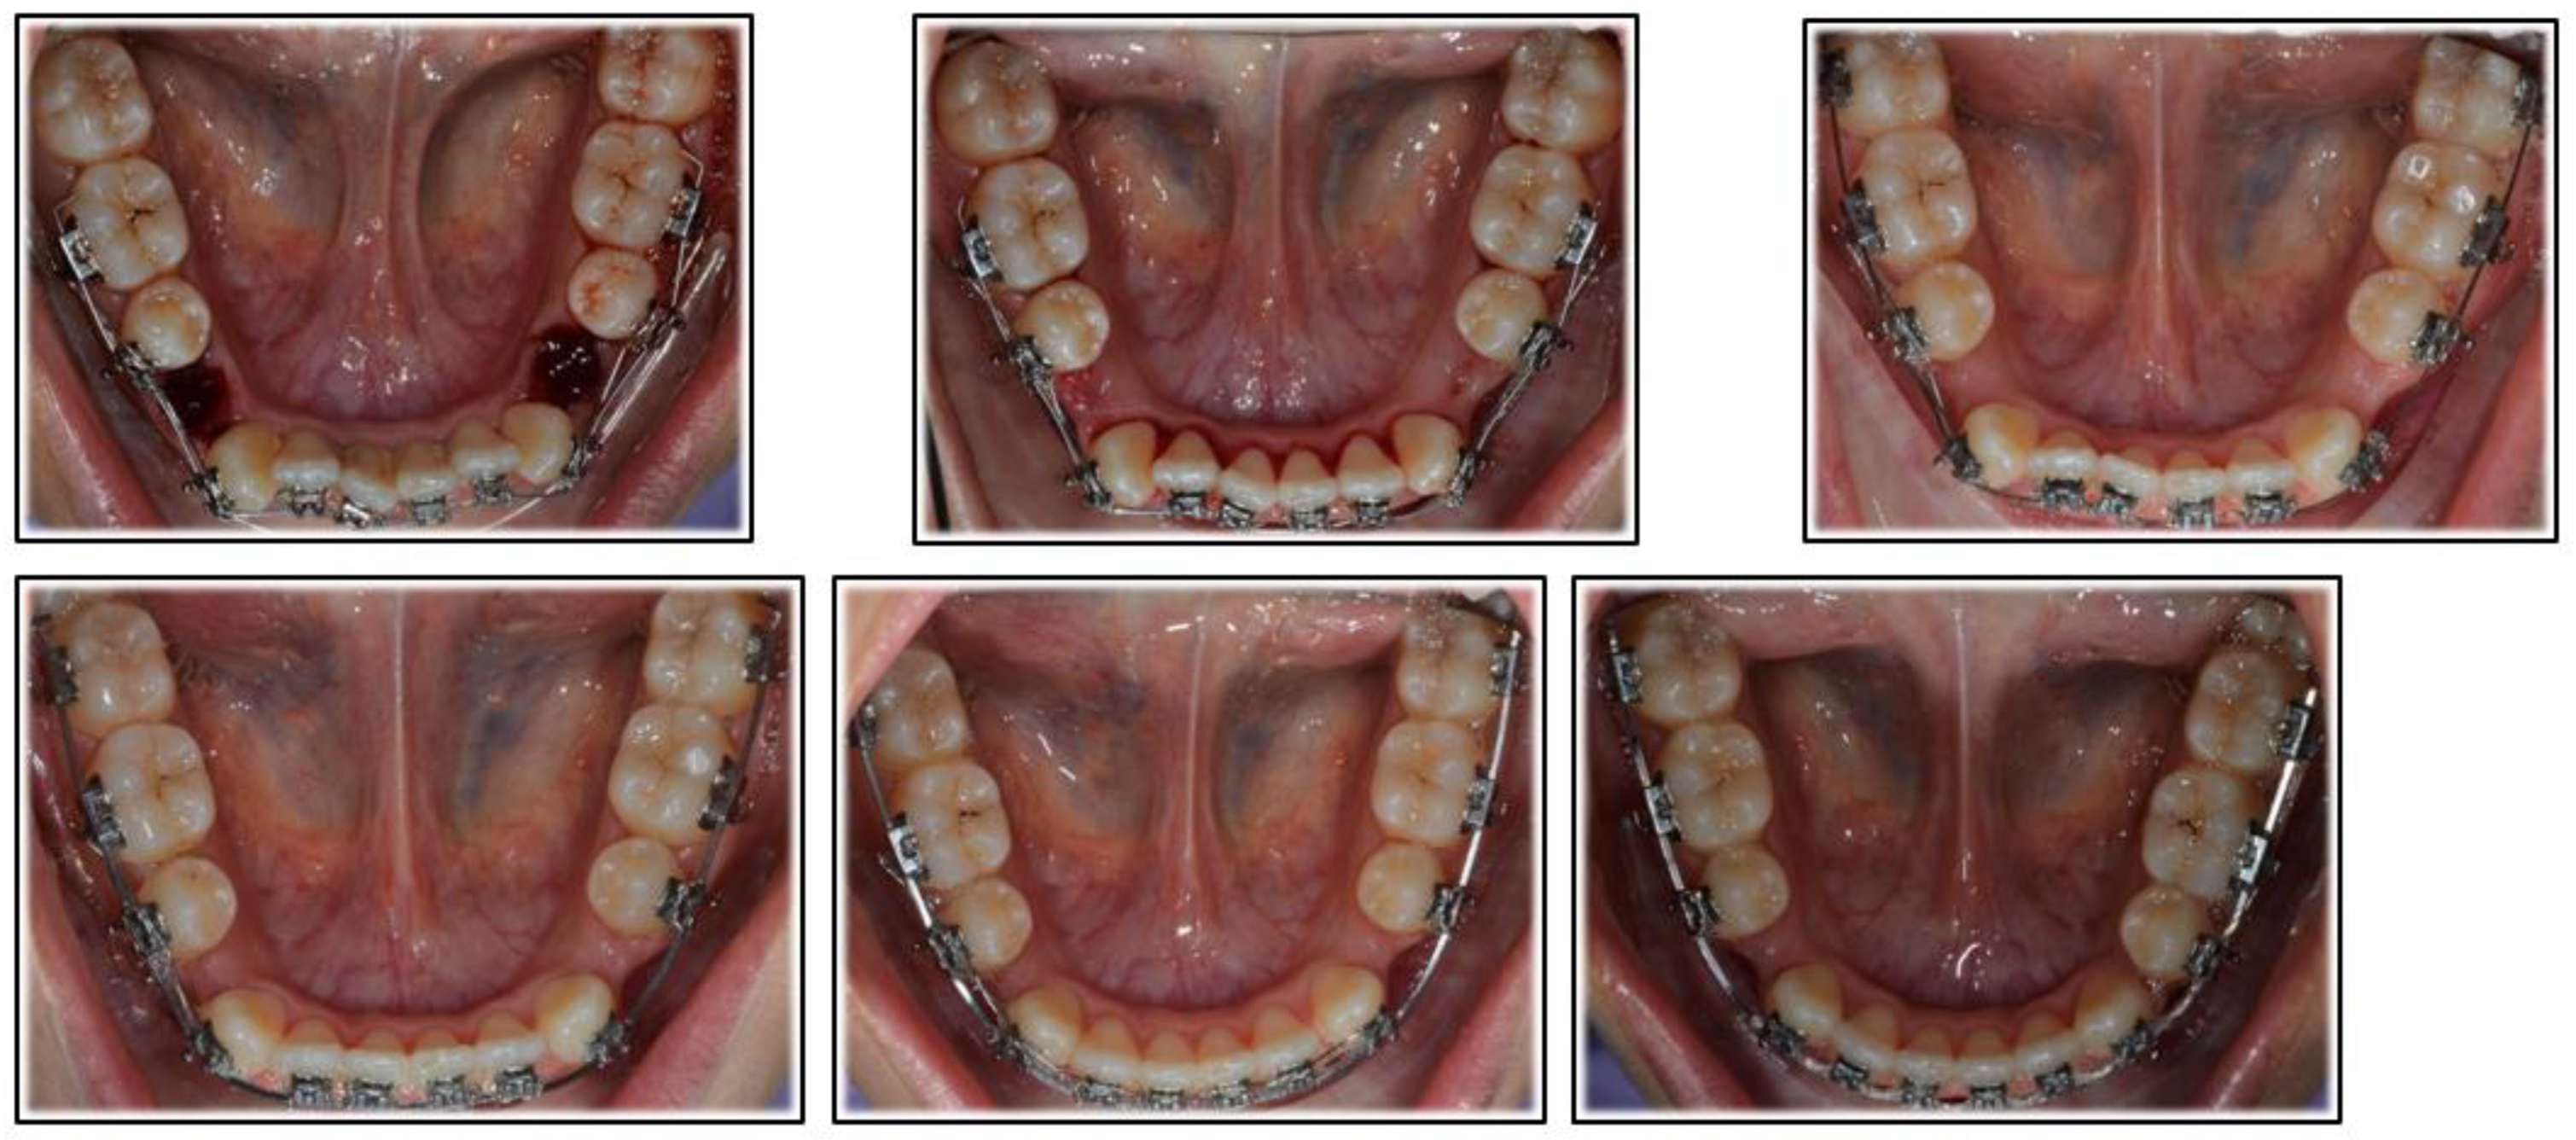

2. Case Report

2.2. Treatment Progress